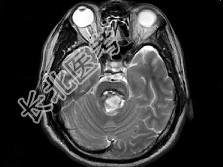

- 单项选择题男,42岁, 头晕视物旋转,面部麻木半月余, 根据所提供图像,最可能的诊断是 ( )

A、脑干动静脉血管畸形

B、脑干出血

C、脑干血管瘤

D、脑干胶质瘤并出血

E、脑干梗死